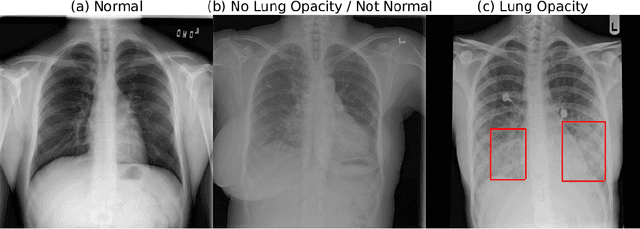

Abstract:Pneumonia is the leading cause of death among young children and one of the top mortality causes worldwide. The pneumonia detection is usually performed through examine of chest X-ray radiograph by highly-trained specialists. This process is tedious and often leads to a disagreement between radiologists. Computer-aided diagnosis systems showed the potential for improving diagnostic accuracy. In this work, we develop the computational approach for pneumonia regions detection based on single-shot detectors, squeeze-and-excitation deep convolution neural networks, augmentations and multi-task learning. The proposed approach was evaluated in the context of the Radiological Society of North America Pneumonia Detection Challenge, achieving one of the best results in the challenge.